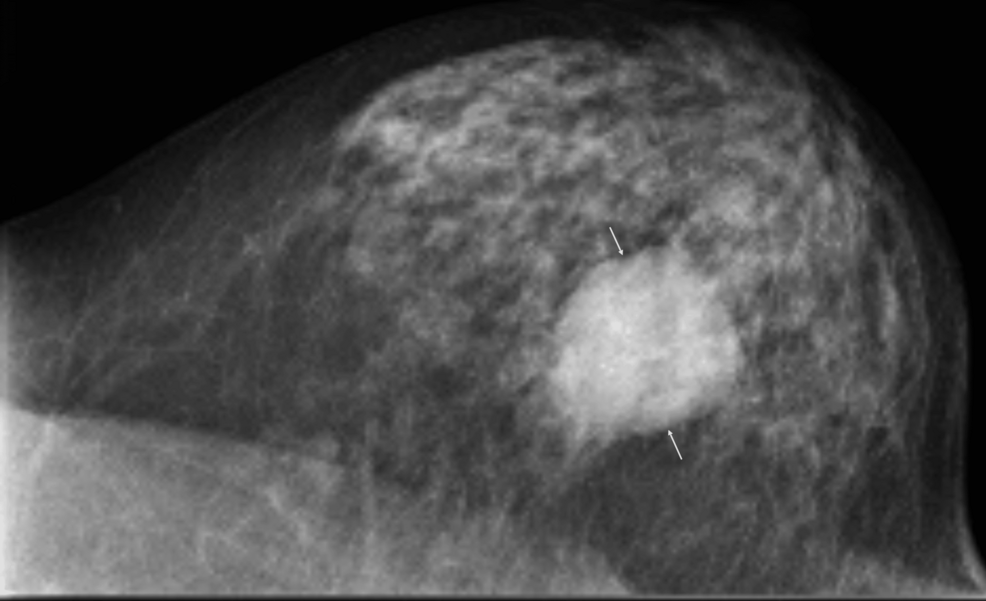

El carcinoma papilar encapsulado (CPE) es una entidad distinta dentro del espectro de tumores papilares de la mama. Las imágenes diagnósticas, como la ecografía y la resonancia magnética, pueden revelar nódulos quístico-sólidos característicos. Histopatológicamente, el CPE se define por una estructura tumoral papilar con una cápsula bien definida.